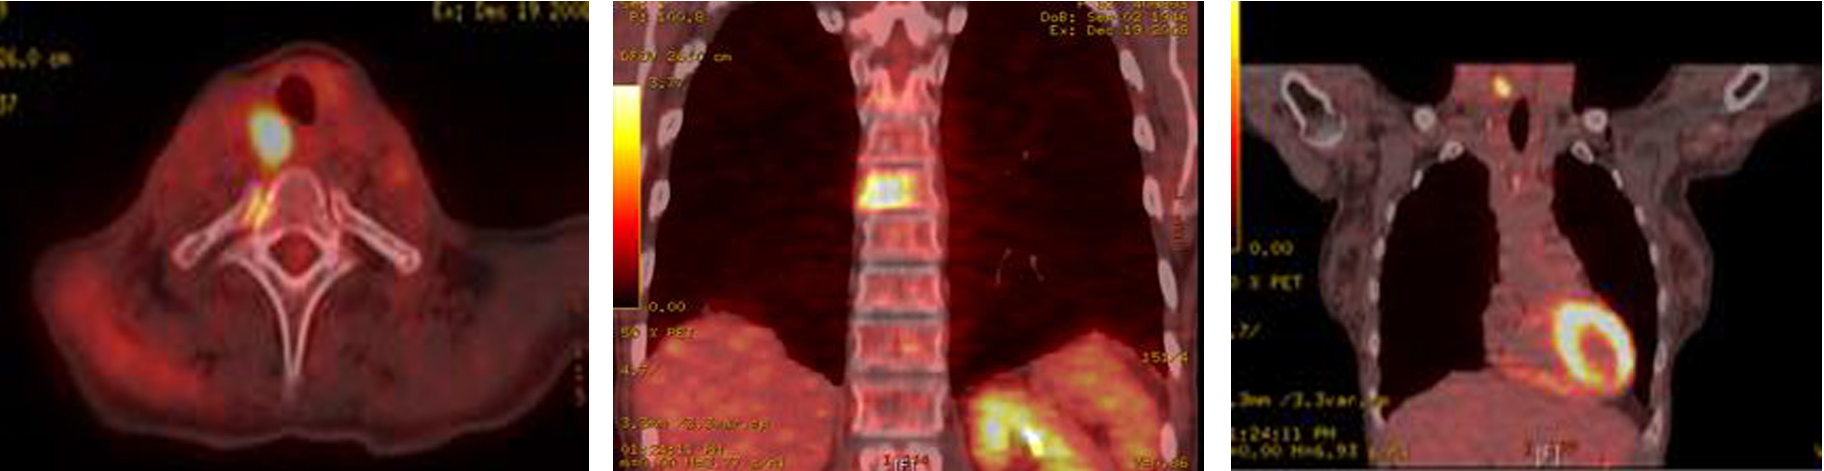

A total thyroidectomy with bilateral lymph node dissection along with superior mediastinal lymph node dissection was performed. Histopathology results confirmed medullary thyroid carcinoma. However, 3 months later, PET-CT showed right tracheoesophageal groove recurrence with diffuse spinal metastasis (Fig. 8).

![]() Click for large image | Figure 8. PET-CT showing extensive metastatic disease involving the spine. |